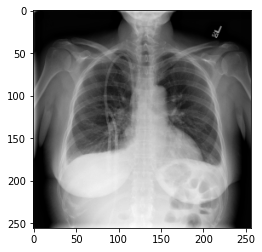

We could plot the images by indexing them on dataset,

e.g., we can plot the first image in the dataset with:

PYTHON

idx = 0

vals = dataset[idx].flatten()

plt.imshow(dataset[idx], cmap='gray', vmin=min(vals), vmax=max(vals))